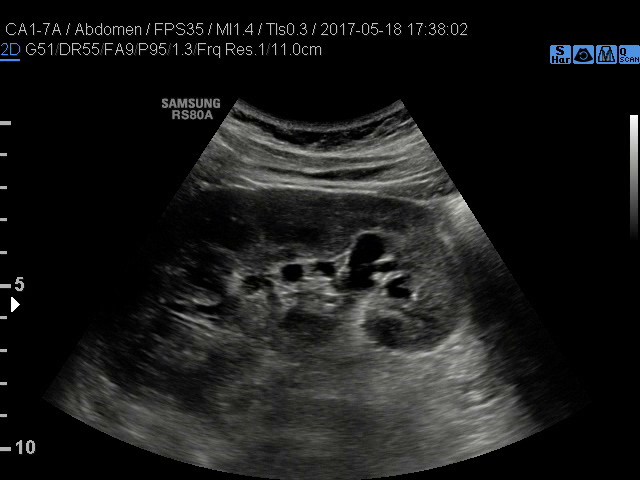

• USG jamy brzusznej

z oceną wątroby, trzustki, nerek, śledziony, pęcherza, gruczołu krokowego, dużych naczyń jamy brzusznej oraz przestrzeni okołoaortalnej.

• USG jamy brzusznej z oceną wątroby, trzustki, nerek, śledziony, pęcherza, gruczołu krokowego, dużych naczyń jamy brzusznej oraz przestrzeni okołoaortalnej